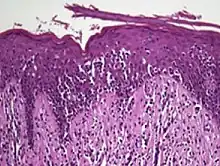

Histology

The criteria for the disease are established on the skin biopsy by the presence of the following:[15]

- Presence of cancer cells with twisted contours (cerebriform nuclei)

- In the patch and plaque stages, the cancer cells are seen in the epidermis (the most superficial layer of skin).[16] This is referred to as epidermotropism.

- Pautrier's microabcesses, aggregates of four or more atypical lymphocytes arranged in the epidermis. Pautrier microabcesses are characteristic of mycosis fungoides but are generally absent.

- In the tumour stage, the cancer cells move into the dermis (the deeper layer of skin)[16]

- Large cell transformation, where clonally identical lymphocytes in the lesion exhibit hypertrophy. In transformed cells, presence of the CD30 receptor is associated with improved survival[17]

Traditionally, mycosis fungoides has been divided into three stages: premycotic, mycotic and tumorous. The premycotic stage clinically presents as an erythematous (red), itchy, scaly lesion. Microscopic appearance is non-diagnostic and represented by chronic nonspecific dermatosis associated with psoriasiform changes in epidermis.

In the mycotic stage, infiltrative plaques appear and biopsy shows a polymorphous inflammatory infiltrate in the dermis that contains small numbers of frankly atypical lymphoid cells. These cells may line up individually along the epidermal basal layer. The latter finding if unaccompanied by spongiosis is highly suggestive of mycosis fungoides. In the tumorous stage a dense infiltrate of medium-sized lymphocytes with cerebriform nuclei expands the dermis.